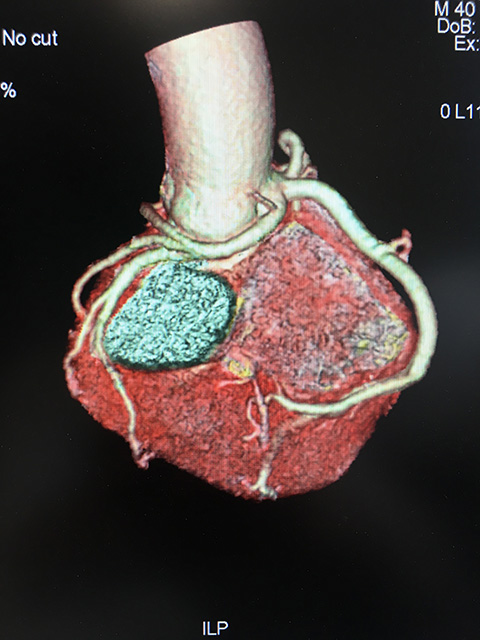

让患者稍作休息后,3月12日,评估患者病情后,李主任再次带领团队为黄先生行冠脉造影,查看冠脉情况,术中冠脉未见明显狭窄,但有意思的是,李主任发现回旋支开口于右窦,与右冠状动脉共开口,向左室前壁绕行,分布于左室侧壁。也就是说,黄先生的心脏血管存在畸形。李主任术中对团队成员说:“这种畸形并不常见,此种畸形应是先天性的,患者现已40岁,血管目前无明显狭窄,血管是可以满足心脏供血的,暂无需特殊处理。”接着李主任再行左室造影,提示左室符合心尖部心肌肥厚图像。至此,黄先生突发心跳骤停,很可能就是心肌肥厚引起的。为了能够更好的查看患者的心肌情况和重建心脏血管,李主任为黄先生进一步进行了心脏核磁共振和冠脉CTA检查,检查提示黄先生的确患有心肌肥厚,黄先生的心跳骤停也很可能是因为心肌肥厚诱发室颤导致的。